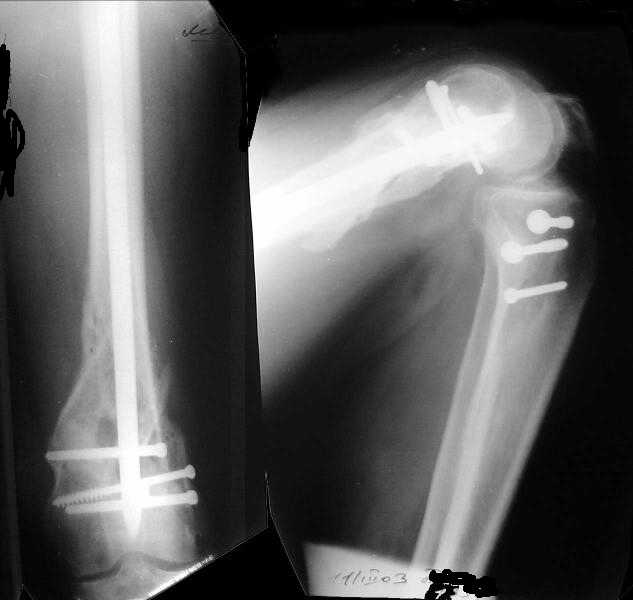

I attached an example of C2 fracture with result of the same technique in 5 months.

This is great. I would never have thought of doing antegrade nailng for such a #. I would also have never dreamt of such range of flexion.